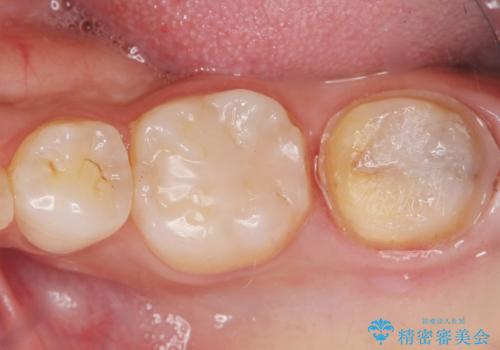

- 奥歯が黒くなっていることを気にされ来院された患者様です。

精査したところ、左下の奥歯にう蝕を認めました。

患者様のご希望により、う蝕を丁寧に除去したのちセラミッククラウンによる補綴治療を行いました。

セラミッククラウンの自然な仕上がりと咬み心地にご満足頂けました。

クラウンの種類:オールセラミッククラウン スタンダード